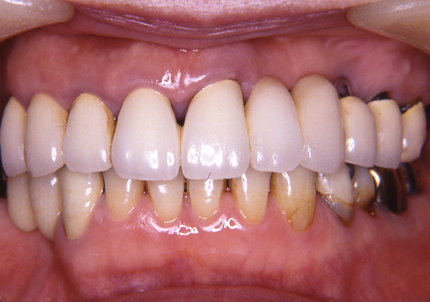

10.上顎補綴物装着(2008年12月)

12.上顎補綴物装着(2009年5月)

16.下顎インプラント補綴治療終了(2017年4月8日)

23.口腔内写真(2024年6月26日)

25.初診より18年経過(2024年6月26日)